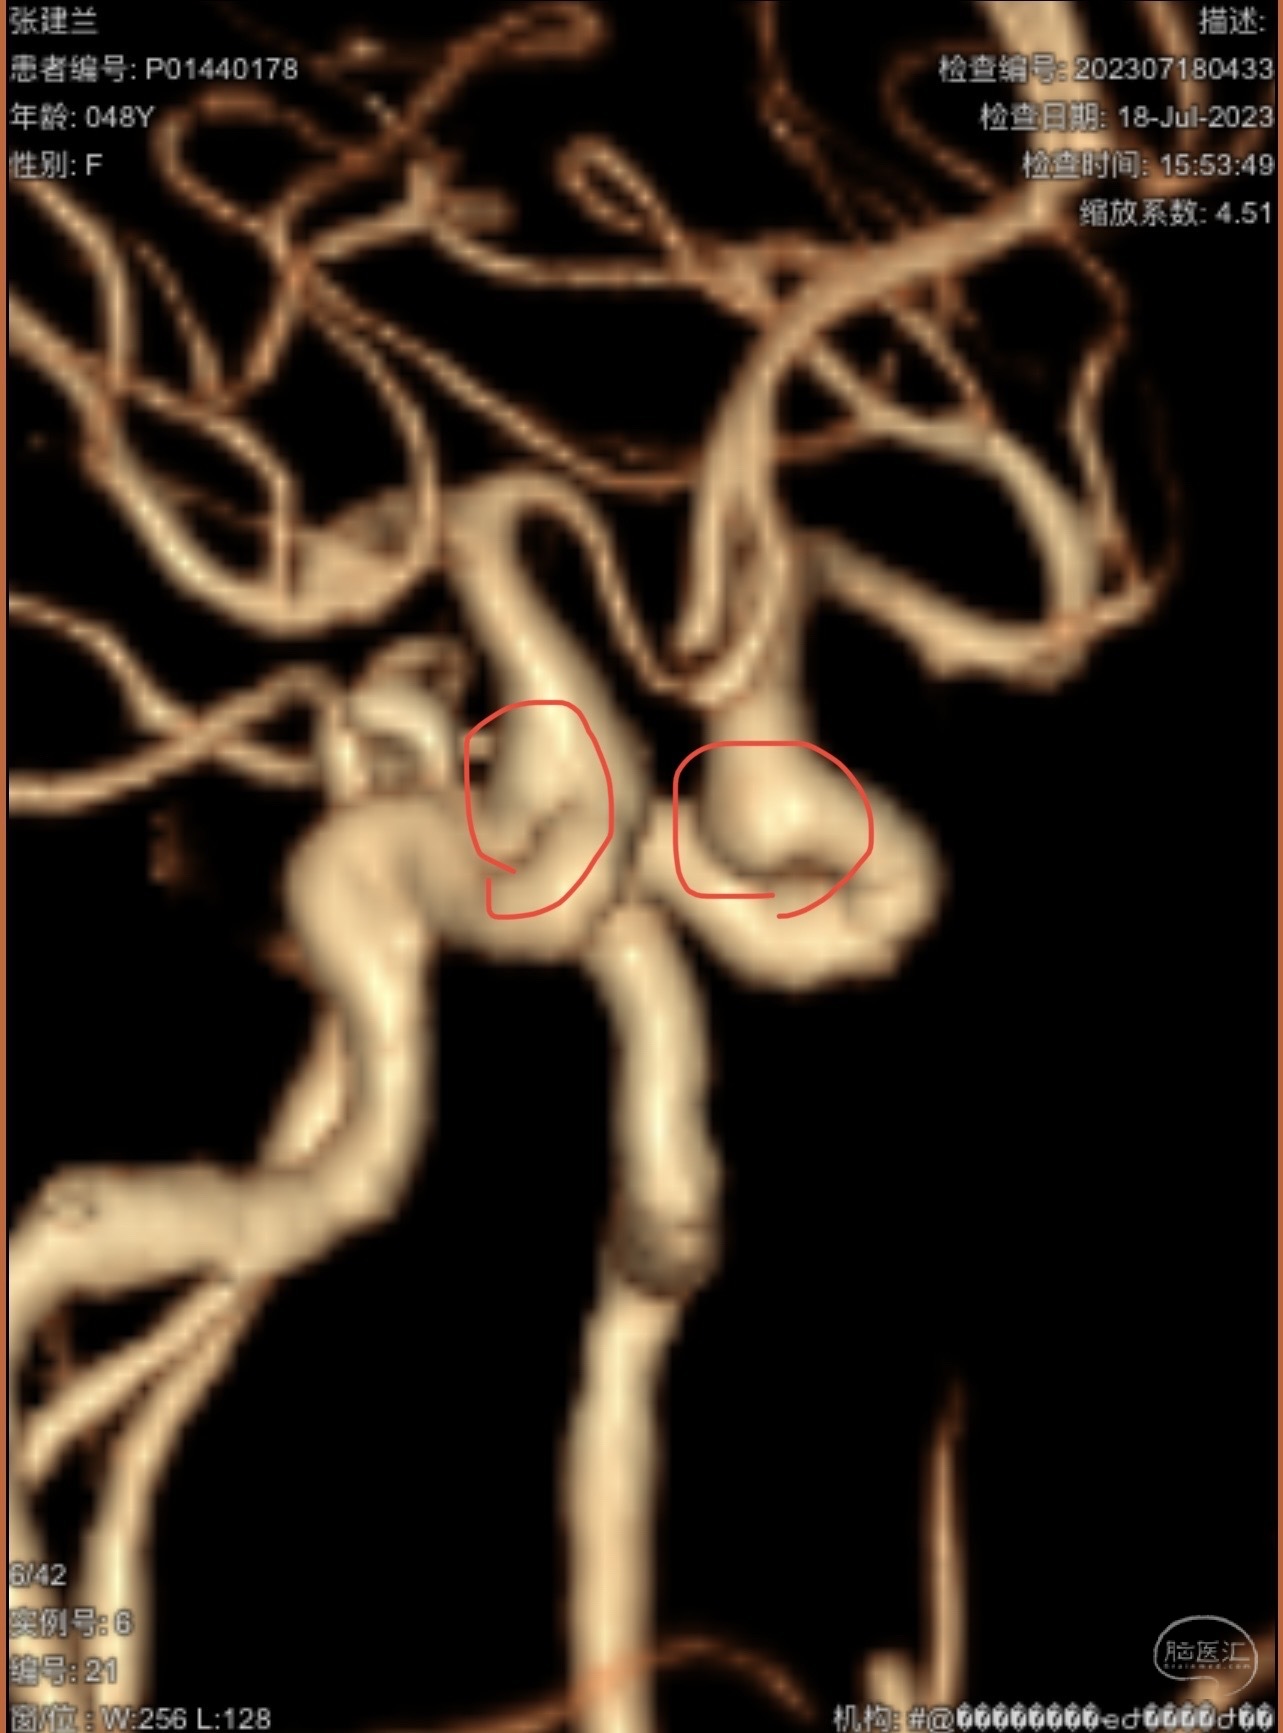

CTA示:右侧颈内动脉C6段见指向下方的突起,余左侧颈内动脉、双侧椎动脉、大脑前动脉、大脑中动脉、大脑后动脉及基底动脉走形正常,未见明显扩张及狭窄,局部未见明显瘤样扩张。

看原图,应该有两侧动脉瘤😅

2023-07-27全脑血管造影:双侧颈内动脉眼动脉段动脉瘤,右侧较大